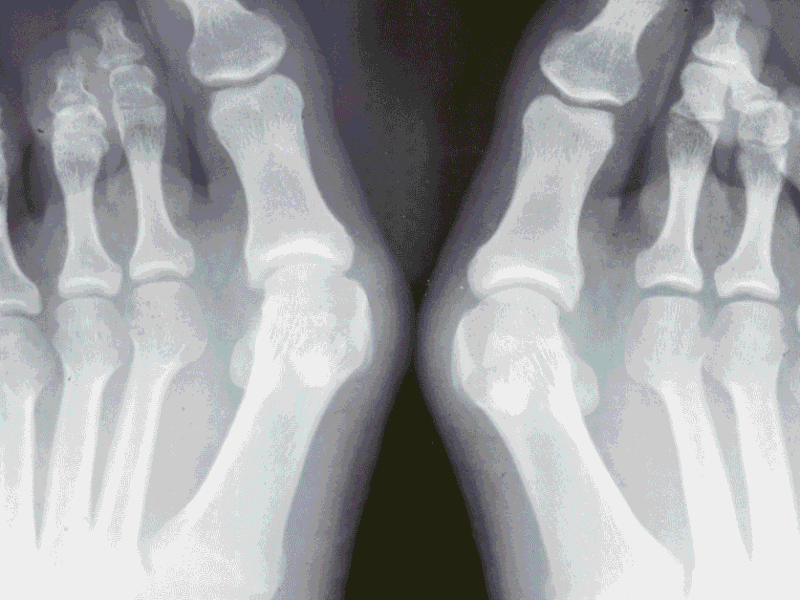

Bunions 101: Everything You Need to Know

A bunion, medically known as hallux valgus, is more than just a bump on the side of your foot. It’s a complex foot deformity that can cause significant pain, mobility issues, and even affect your quality of life if left untreated. In this comprehensive guide, we’ll explore what bunions are, how they develop, their symptoms, [...] Read More